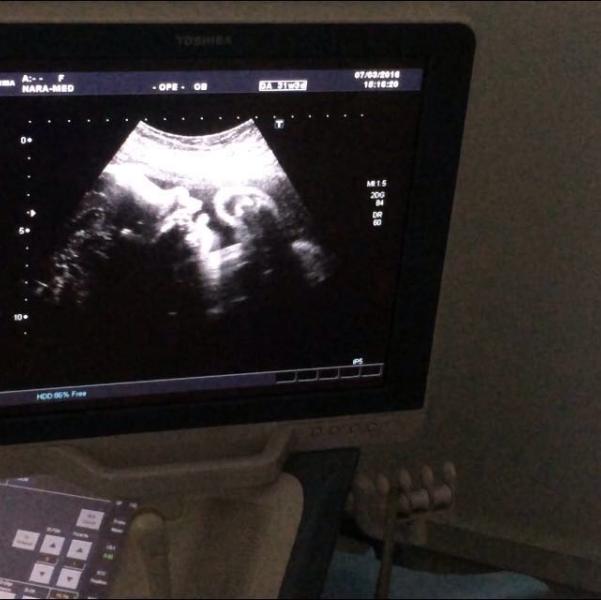

Итак!Третье плановое узи!❤️

Нам 31 неделя и 3 дня!😍

Делали в Нара Мед!✅

Мы с мужем в восторге!👍

Узистка Салова-супер специалист!👌В общем впечатления исключительно положительные!🙏☝️Жаль,что не ходили в нарамед раньше!Посмеялись все вместе как Максимка показывал нам язык и сосал руку!😝👍Узистка сказала, что сразу по личику видно,что мужичек!😋И что наш мальчик красивый губастик с большим достоинством!😅💪(фото в комментах)

Вес 1600!👌Кровотоки в норме!

Лежит правильно!✅